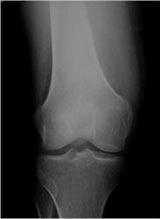

Plain X-Rays:

- Diaphyseal lesion on external surface of bone; medullary canal uninvolved

- Radiolucent mass extending into surrounding soft tissues

- Saucerized cortex with chondroblastic soft tissue mass that is usually primarily radiolucent on plain X-rays

- Periosteal reaction usually most evident feature on surface of bone (Hair on End or Sunburst appearance with spiculated pattern of calcification oriented perpendicular to the bone)

- Cortical thickening at margins of erosion (40%)

- Rarely may have Codman’s triangle

- Spiculated or sunburst periosteal reaction (due to periosteal elevation)

- Partial matrix mineralization may be seen consistent with

- chondroblastic nature

- Rare intramedullary invasion